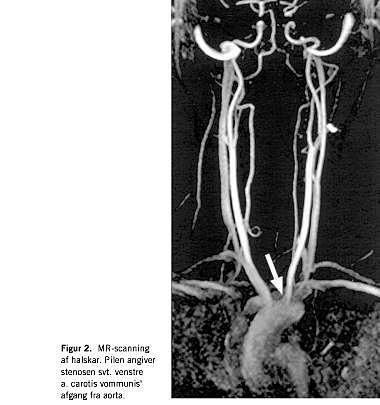

En 42-årig, tidligere rask kvinde af dansk afstamning blev indlagt på mistanke om apopleksi. Forud for indlæggelsen havde patienten haft hovedpine og tilbagevendende tilfælde af 1-2 minutters varighed med følelsesløshed og tyngdefornemmelse i de højresidige ekstremiteter, efterfulgt af nedsat kraft og styringsbesvær. Der var ingen familiære dispositioner for tromboemboliske sygdomme. Tobaksforbruget var på 10-15 cigaretter daglig. Hun anvendte ikke hormonel antikonception. Objektivt fandtes højresidig central facialis parese samt nedsat kraft i højre underekstremitet. Der påvistes leukocytose, uden C-reaktivt protein eller sænkningsreaktionsforhøjelse. En magnetisk resonans (MR)-skanning af cerebrum, et elektroencefalogram og en spinalvæskeundersøgelse viste alle normale forhold, og efter 12 dages indlæggelse blev patienten udskrevet. Hun blev genindlagt fem uger senere med ekspressiv afasi og kramper i begge underekstremiteter. En computertomografi af cerebrum viste infarkt ved venstre capsula interna. En ultralydundersøgelse af halskar og hjerte viste, at de var uden embolikilder. På mistanke om postinfarkt epilepsi blev patienten sat i behandling med oxcarbazepin. I efterforløbet fik hun urtikaria og Coombs negative hæmolyse (medikamentelt betinget?). oxcarbazepin blev erstattet med clonazepam, og der indledtes højdosis prednisolonbehandling. Objektivt fandtes nu mislyd under begge claviculae. Blodtrykket var normalt (120/70) på begge arme. På mistanke om TA blev der foretaget MR-angioskanning af cerebrum og halskar, hvorved der påvistes stenose på hhv. venstre a. cerebri media (Figur 1 ) og venstre a. carotis communis ved afgangen fra aorta (Figur 2 ). Ved trombofiliudredning fandtes patienten homozygot for FVL, hvorfor antikoagulantiabehandling blev iværksat. Patienten blev overflyttet til reumatologisk afdeling, hvor der efterfølgende fandtes forskelle i blodtrykket (højre: 139/84, venstre: 118/75). Efter yderligere tre ugers steroidbehandling hørtes mislydene ikke længere.